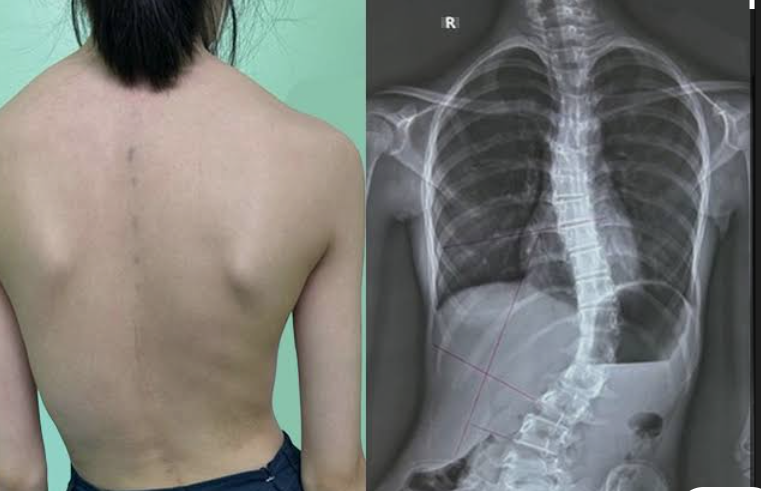

From the moment Ivey was diagnosed with scoliosis, I knew our lives were about to change forever. 🤍 The word itself felt heavy, frightening—something no parent is ever ready to hear. But even then, I could never have imagined the strength my daughter would reveal as the journey unfolded.

At just 11 years old, Ivey was fitted with a rigid back brace. Her movements were restricted, her comfort taken away, and her once carefree world suddenly felt smaller. Simple things—sitting, sleeping, moving—became daily challenges. Yet somehow, her spirit never bent. Through it all, she kept dancing, laughing, and embracing life with a courage far beyond her years 💪✨. While her body was learning limits, her heart refused to accept them.

The day of her surgery is etched into my soul. As she was taken into the operating room, my breath caught in my chest. For eight long hours, time stood still. Every second felt endless. And then… she came out. Taller. Straighter. Stronger than ever before. 🏥🌈 In that moment, I didn’t just see my child—I saw a warrior who had fought bravely for her future.